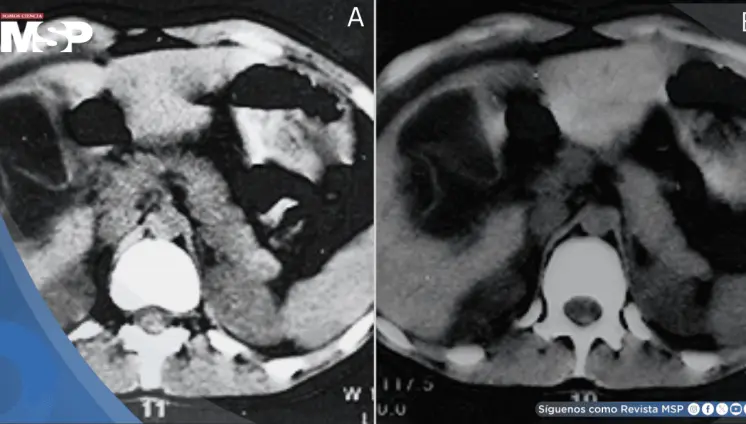

La paciente presentó cambios en el hábito intestinal y sangrado rectal con imágenes compatibles con lesiones estenosantes, inicialmente sospechosas de neoplasia sincrónica.

El estudio histológico confirmó un adenocarcinoma mucinoso de células en anillo de sello de vejiga con invasión muscular y diseminación metastásica pulmonar y ósea.